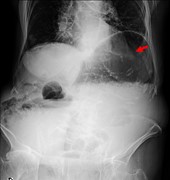

Abdominal pain and hematuria: duodenal perforation from ingested foreign body causing ureteral obstruction and hydronephrosis

Nina Kolbe and others

Journal of Surgical Case Reports, Volume 2016, Issue 2, February 2016, rjw018, https://doi.org/10.1093/jscr/rjw018